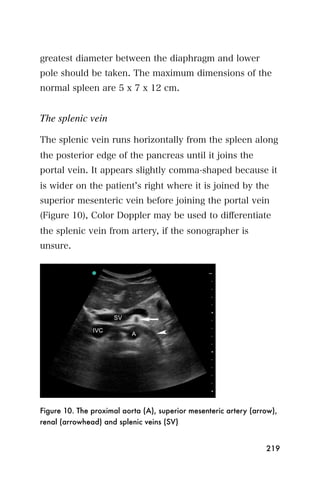

In polycystic kidney disease, the normal architecture of

both kidneys is disturbed, and the kidneys appear

enlarged due to the presence of many cysts of different

sizes and shapes (Figure 9). Patients with this disease

need referral to a kidney specialist.

234